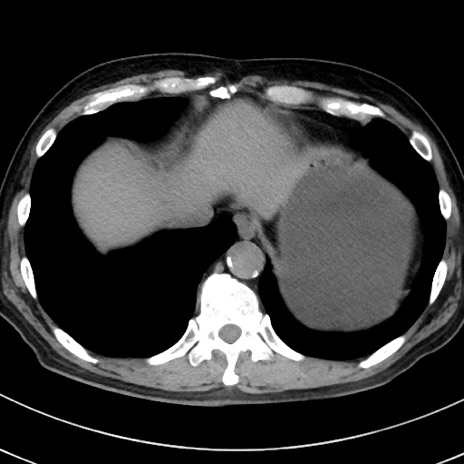

冠状断像

【症例】70歳代 男性

【主訴】腹痛・嘔吐

【現病歴】昨晩より、嘔吐・腹痛あり。今朝になっても嘔吐あり。来院。

【既往歴】心臓バイパス手術、開腹胆摘、腸閉塞

【身体所見】BP 107/71mmHg、HR 116/min、腹部:平坦、軟、下腹部に軽度圧痛あり。反跳痛なし。

【データ】WBC 15100、CRP 0.32